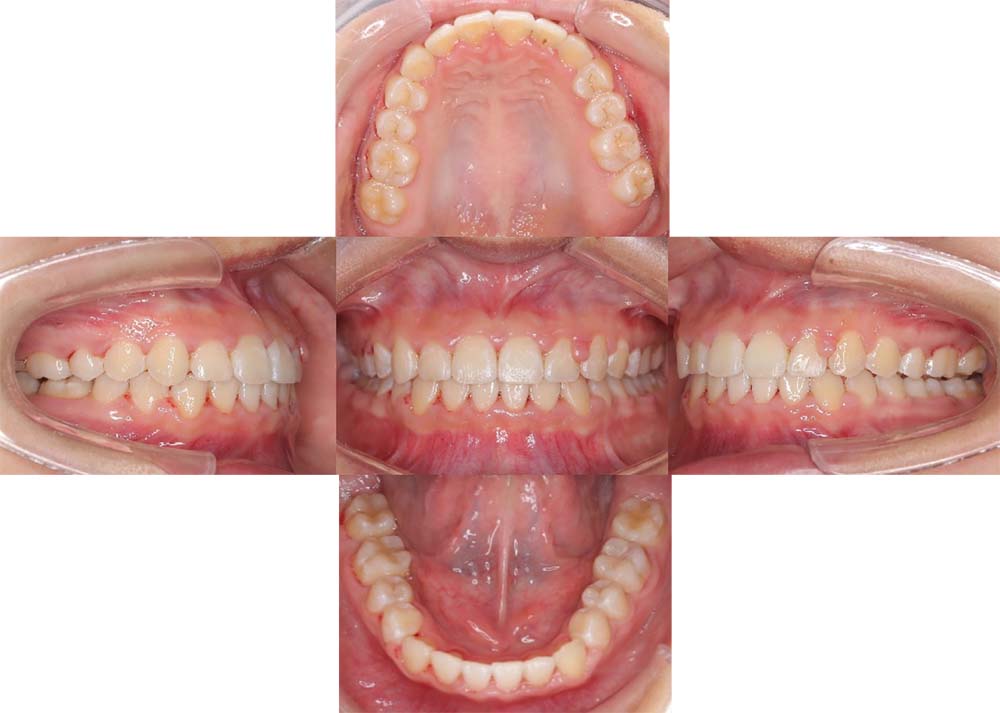

症例01

| 主訴 | 歯並びがガタガタしている。 |

| 診断名あるいは主な症状 | 叢生 |

| 年齢/性別 | 22歳・男性 |

| 矯正ステージ | 大人の矯正治療 |

| 治療方法 | ワイヤー矯正 |

| 抜歯部位/抜歯有無 | 非抜歯 |

| 治療内容 | 上顎大臼歯の遠心移動により前歯のガタガタを排列スペースを獲得し全顎的な排列を行った。 |

| 費用 | 85万円程度(2025.10時点の料金となります。) ※矯正基本料金、審美ブラケットを含む |

| 治療期間 | 2年4ヶ月 |

| 主なリスク・副作用 | 痛み、歯根吸収、歯肉退縮、虫歯、後戻り |